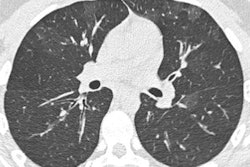

Chest radiograph reported as normal. Note the diffuse ground-glass shadowing in all zones. Images courtesy of Dr. Patrick Liu-Shiu-Cheong, Dr. Owen Dempsey, and BMJ Case Reports 2019."Our patient's CXR [chest x-ray] report was initially reported as normal (although we disagreed)," the authors wrote. "He subsequently had a CT pulmonary angiogram with high-resolution reconstruction (to exclude pulmonary thromboembolic as well as interstitial lung disease), reported as showing a ground glass, mosaic pattern in both lungs, with borderline enlarged hilar nodes, presumed reactive."

CT scan shows mosaic pattern; apical axial view.